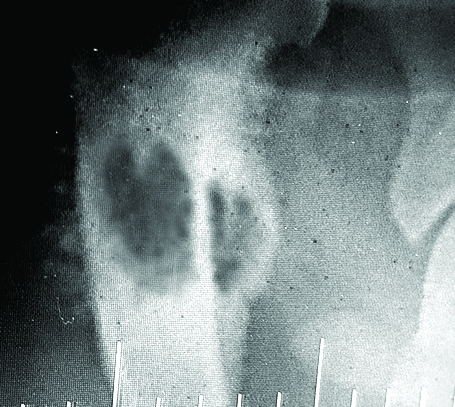

Bone cancer. How could he have bone cancer? He is only 4 years old. He has a great pedigree. He has nothing like bone cancer in any of his family history. We have been doing ministry together for 3 of his short 4 years of life. He cannot have bone cancer! Yet, there it was on the large screen in front of him. The Vet he had been referred to is close friends with the Oncology Department Head at the local university. They had conferred and he had agreed 100%. It was advanced and it was aggressive. “Act now or lose your dog in weeks. They can take him tomorrow at the university but that will cost ten to twelve thousand dollars. Or, we can remove the leg tomorrow. That will cost about four thousand,” the vet told him flatly.

In a split second, Tim thought he heard in his heart that “still, small voice” that people talk about. He was reminded of a story he had heard a decade or more before in which God had fixed a man’s guitar. The entire story flooded back to him in an instant and he thought he heard God say, “If I care enough about a man and his guitar, then I care enough about a man and his dog.” That was it. Wait. That was it? God, can’t you be a little more specific? Can’t you write on the wall or something? Does that mean you’re going to heal Winston or does that mean…. what does that even mean?